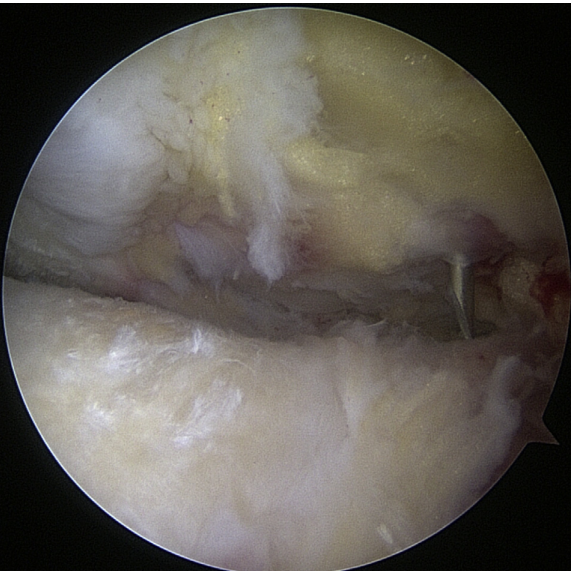

Standard Portal Placement

A traditional posterior portal would be placed at the “soft spot” of the infraspinatus’s raphe. The standard placement is 2 centimeters inferior and 2 centimeters medial to the posterolateral border of the acromion, however this can change according to the patient’s size. It is possible to make a portal incision after inserting an 18-gauge spinal needle into this region to roughly follow the correct course. The posterior capsule is shattered by inserting a blunt trocar into the joint and directing it toward the coracoid.6

Preliminary surgical planning will establish the exact location of the anterior portal. Arthroscopy techniques for rotator cuff or biceps tenodesis usually include positioning the anterior portal centrally in the rotator interval, near the subscapularis tendon. It is common practice to use two anterior portals while performing arthroscopy on labral disease. The anteroinferior portal, which is often the working portal, is typically located around the subscapularis tendon. An extra portal called the anterosuperior portal may be used for suture inspection or shuttletling without damaging the supraspinatus tendon. Its location is directly above the biceps tendon or just slightly ahead of it. A common technique for creating these portals is the “outside-in” approach, which involves inserting a spinal needle under direct arthroscopy view to determine the correct portal location.6

Setup

The coracoid, acromioclavicular joint, clavicle, and acromion are all marked on the skin. If subacromial work is going to be performed, the subacromial bursa may be infiltrated with up to 30 cm3 of a mixture of 0.25% bupivacaine and epinephrine. A standard posterior portal is the typical site of access to the subacromial area and glenohumeral joint. The typical placement of this opening is 2 centimeters medial and 2 centimeters distal to the posterolateral border of the acromion. Palpating the soft tissues of the posterior glenohumeral joint is a common way to confirm the proper position. An anterior portal develops after the joint has been inserted. Figure 4 shows that the surgeon has the option of employing a spinal needle to perform it from the outside in or an inside out approach, depending on his or her choice. The anterosuperior portal is located just off the outside edge of the acromion. You may find the anteroinferior portal directly on the side of the coracoid. One centimeter below the anteroinferior portal is the 5 o’clock portal, which is defined as passing through the subscapularis tendon. Scientists say this entry point is the most common and least invasive as it mimics neurovascular systems. Any anterior portal may be used to conduct basic shoulder arthroscopy. Figure 5 shows the setup of both anterior portals for biceps tenodesis, subscapularis repairs, and labral repairs. For posterior labral repairs, spinal needle localization allows for the creation of an auxiliary posterolateral portal situated immediately distal to the posterolateral limit of the acromion. Anterior positioning of the Wilmington portal, one centimeter laterally to the posterolateral margin of the acromion, is recommended for superior labral repairs. The posterolateral and Wilmington portals are types of trans-rotator cuff tendon access points. Cannulas with the smallest diameters necessary should be used.25

The subacromial region may be accessed via the posterior portal if needed after any intra-articular procedures are finished. Spinal needle localization allows for the creation of a lateral portal, typically 2 cm laterally to the acromion’s lateral border and aligned with the clavicle’s posterior border (Figure 6). For any subacromial surgery, pre-positioned anterior portals may be used (Figure 7). An extra Neviaser portal may be made underneath the spinal needle localization, precisely below the acromioclavicular joint, if that becomes essential. This may be useful for a variety of suture procedures, including those involving the superior labrum, the rotator cuff, and the decompression of the suprascapular nerve (Figure 8).25